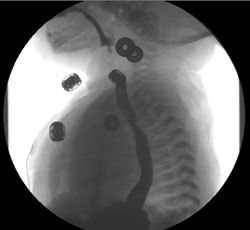

A complete blood cell count and electrolyte levels were normal. A chest radiograph was normal. A barium swallow study was performed because of concern for a congenital airway anomaly. Other conditions considered in the differential diagnosis included a vascular ring and sling. The barium swallow study revealed tracheal and esophageal compression, which was consistent with an aberrant right subclavian artery. (The buttons on the baby’s gown are also visible in the image.)